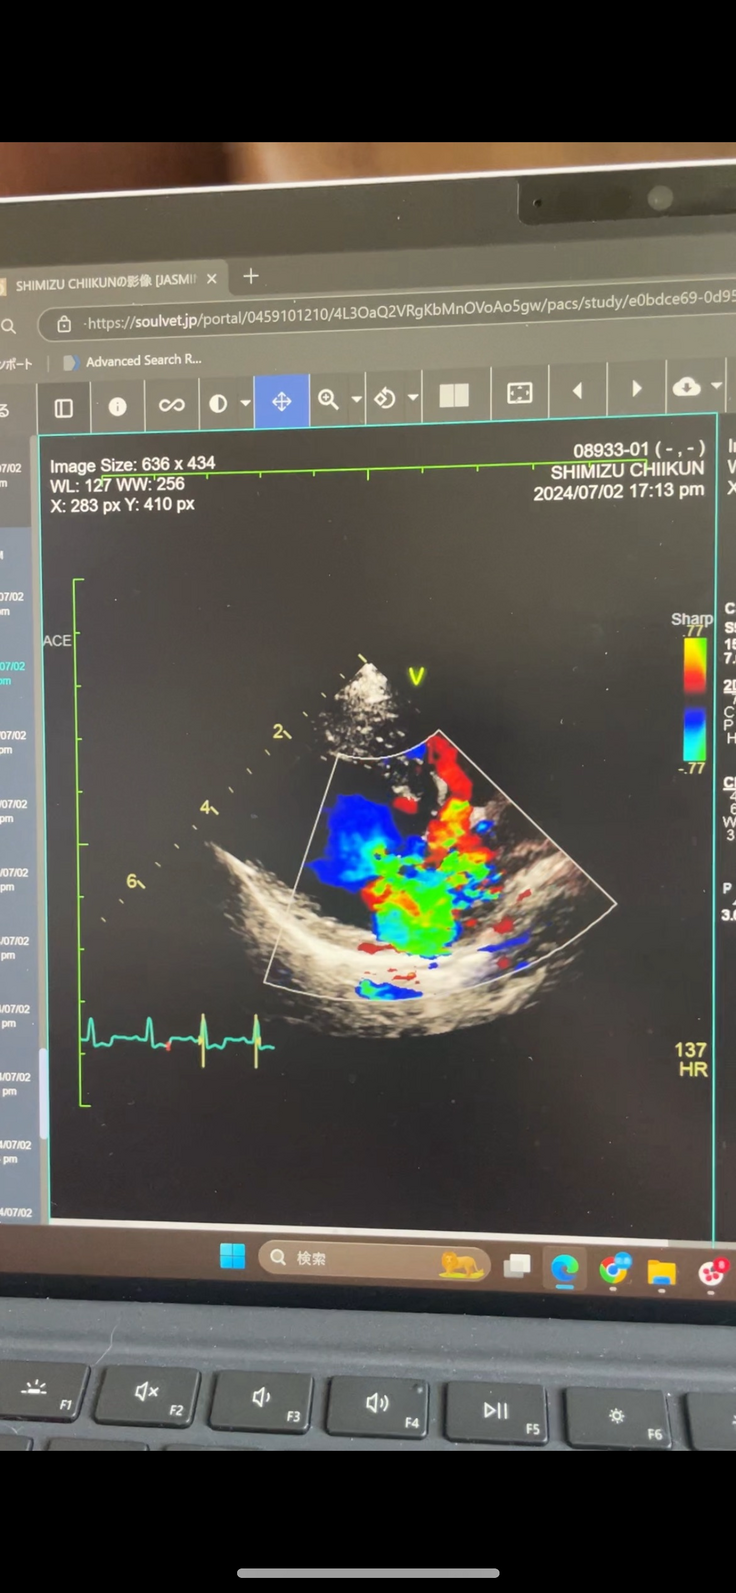

今回チーくんの僧帽弁閉鎖不全症の術後2回目の検診に行ってきました。

結果から話しますと心臓は前回よりさらに小さくなり逆流も問題ないとの事でした😭

手術前のエコー写真(7月)↓↓↓

手術前のエコーと比べるとほんとに良くなってるなと感じます